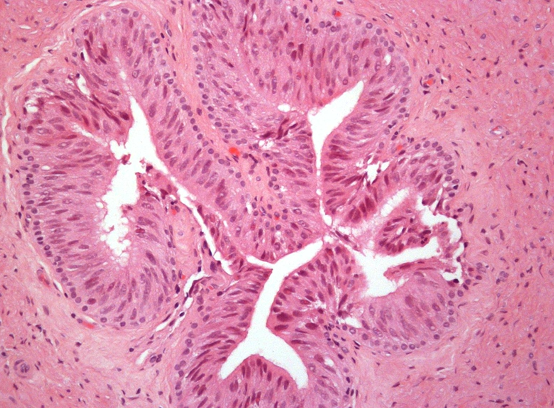

Testis - what is shown here? (in biopsy)

Biopsy of Testis - what is shown?

When doing a biopsy of testis, what is an issue?

The part of tissue is not always truly representative of the whole tissue - some part that you biopsy may be artefact - only see some part mean you may not see all - variations between different seminiferous tubules are present